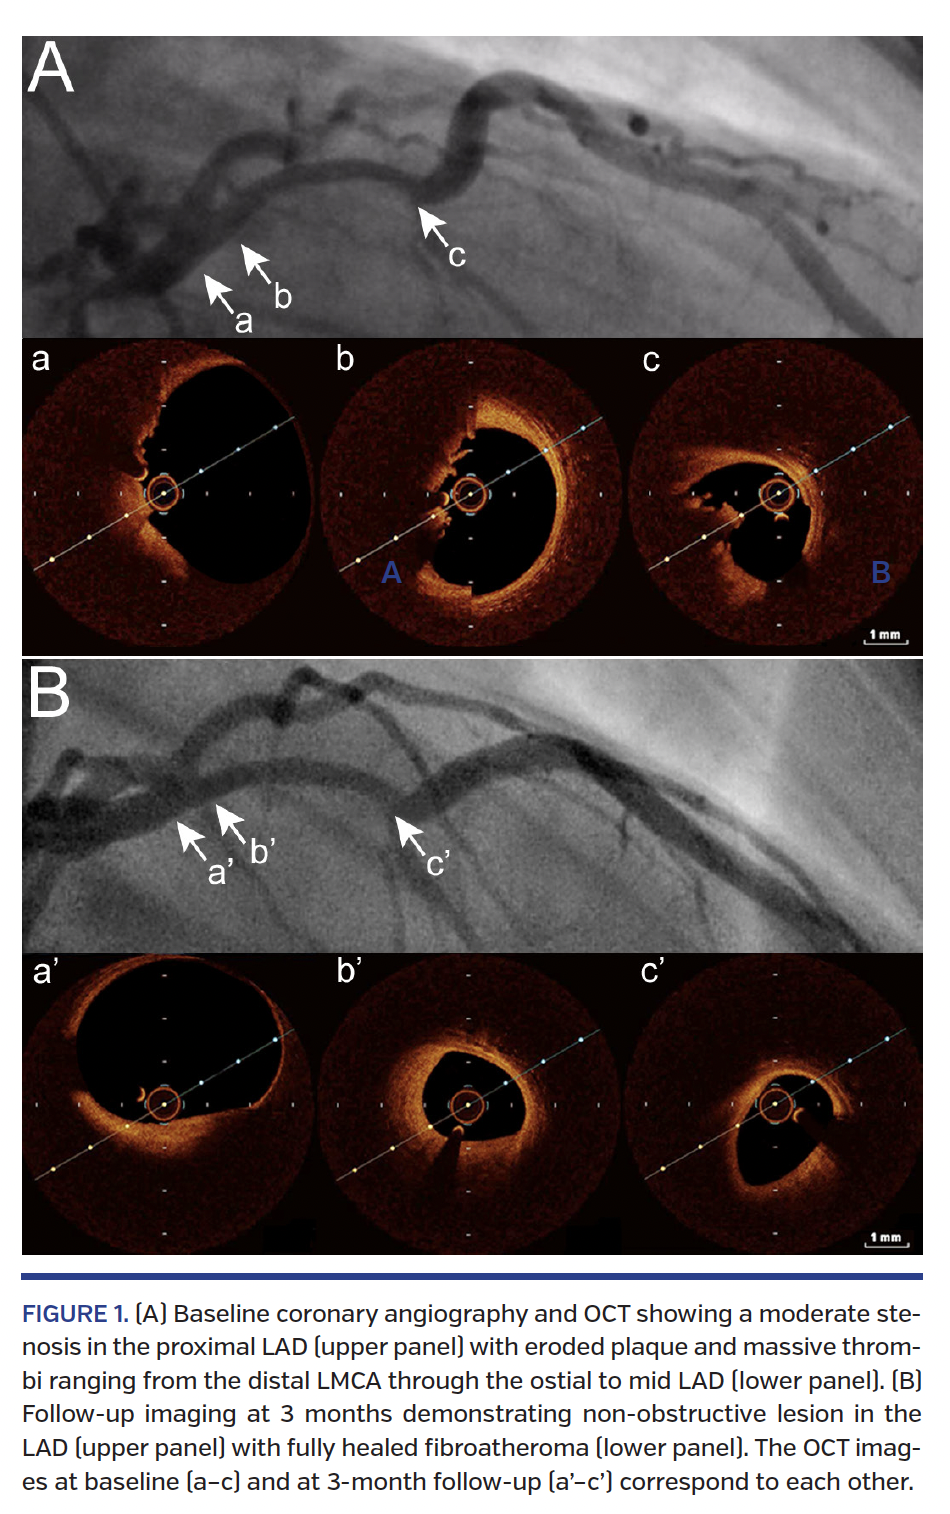

A 22-year-old, obese male smoker with untreated hyperlipidemia and family history of coronary artery disease presented with chest pain and ST-segment elevation in anterolateral leads at ECG following heavy marijuana and alcohol abuse. Coronary angiography showed a moderate stenosis in the proximal left anterior descending (LAD) coronary artery along with distal embolization (Figure 1A; Video 1). No concomitant coronary stenoses were noted, and TIMI 3 flow was present in the LAD. Optical coherence tomography (OCT) revealed plaque erosion with massive thrombi involving the distal left main coronary artery (LMCA) and ostial to mid LAD (Figure 1A; Video 2), along with preserved lumen area of the LAD. Given the diffuse extent of non-obstructive CAD involving the LMCA on OCT, aggressive medical thera-py with glycoprotein IIb/IIIa blocker, aspirin, ticagrelor, and high-dose statin was initiated. At discharge, cardiac magnetic resonance (CMR) imaging showed subendocardial infarction in the basal anteroseptal and lateral walls, and transmural infarction in the apex (Figure 2). After 3 months, repeat angiography with OCT demonstrated a non-obstructive lesion with fully healed fibroatheroma (Figure 1B; Videos 3 and 4). At 7 months, the patient was asymptomatic and control CMR showed preserved left ventricular function with resolution of myocardial edema (Figure 3; Video 5).

Data are limited on the treatment options for myocardial infarction with eroded coronary plaque. Herein, we present the favorable outcome of an OCT-guided watchful-waiting strategy to avoid the invasive treatment of the LMCA in a very young patient with massive coronary thrombosis.